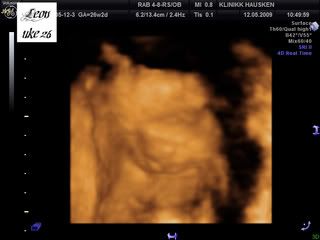

Så, her er bildene av gutten vår:

Han ble målt til å være nesten 1100 gram allerede nå! Det betyr at han er 14 % over gjennomsnittet! Så legen på Hausken ville ha meg til glukosebelastningstest for å utelukke svangerskapsdiabetes[&:] Jeg er egentlig i høy risk for det, i og med at jeg har PCOS, var noe overvektig før graviditet, og jeg har diabetes type 2 i familien.